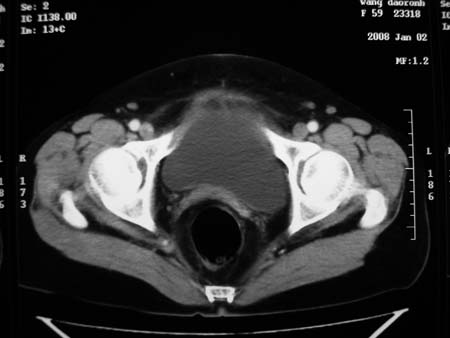

以下是引用卜一在2008-1-2 20:39:00的发言:[br]右侧附件区囊实性肿块,与膀胱壁分界不清,增强后实性部分显示强化。考虑为:右侧卵巢囊腺癌可能性大。支持!

以下是引用zhengfaming在2008-1-2 19:28:00的发言:[br]右下腹腔内附件区可见一囊实性混合密度块影,先考虑囊腺癌